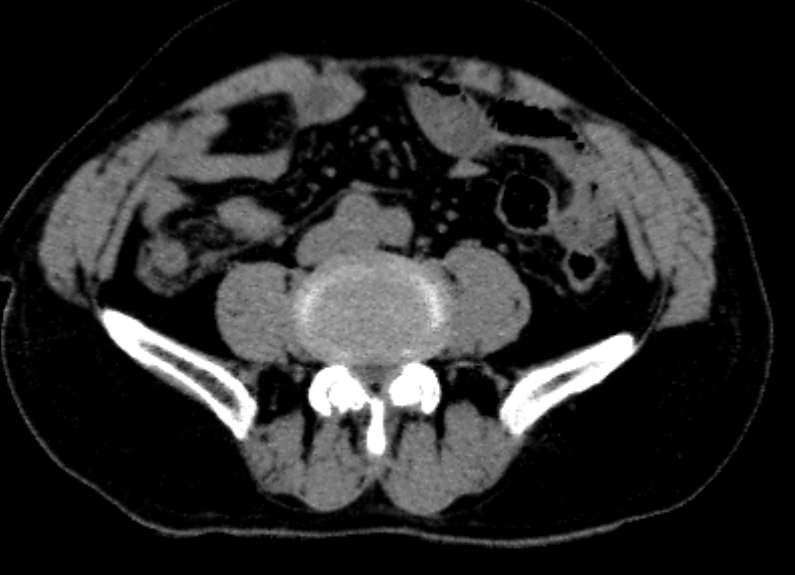

血常规白细胞:11.68*10^9/L,中性粒细胞比率89.5%,C反应蛋白26.46mg/L,血清淀粉样蛋白219.04mg/L。CT示:1.考虑阑尾炎性病变,请结合外科会诊及实验室检查2.升结肠周围脂肪间隙模糊,考虑炎性病变。

4.辅助检查:血常规白细胞:11.68*10^9/L,中性粒细胞比率89.5%,C反应蛋白26.46mg/L,血清淀粉样蛋白219.04mg/L。CT示:1.考虑阑尾炎性病变,请结合外科会诊及实验室检查2.升结肠周围脂肪间隙模糊,考虑炎性病变。